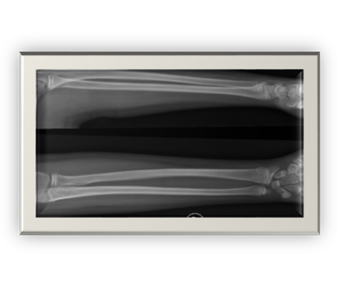

Fractura tipo Suprametafisaria con su progresión hasta la consolidación 1-4